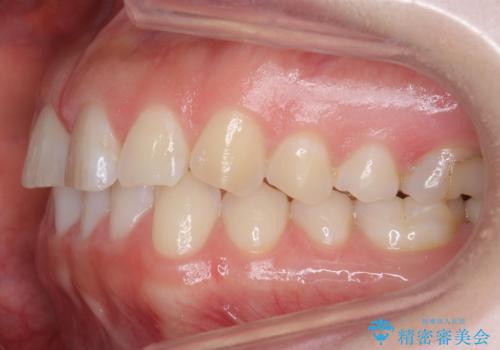

下の前歯のちょっとしたがたつきを治したい

- 下の前歯のがたつきを治したいとのことでした。

上の前歯のちょっとしたねじれも治療しています。

軽度だったため、部分矯正のコースで短期間で治療しました。

下の歯並びを並べるため、わずかに歯を削合しています。

そうしないと、前に出て上の前歯に強く当たってしまうためです。また、後戻りを防ぐ効果もあります。